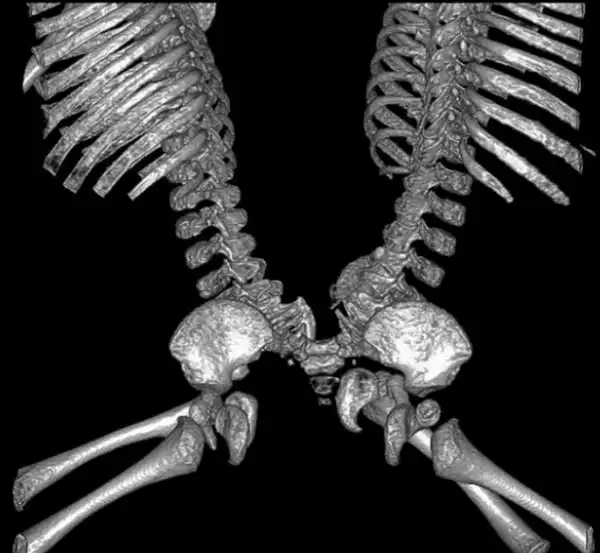

Темнокожие мальчики Иисус и Иаков родились на свет соединенными спина к спине в области таза и нижней части позвоночника. Часть желудочно -кишечного тракта у них тоже была общей. В остальном же они были полностью функциональны и здоровы.